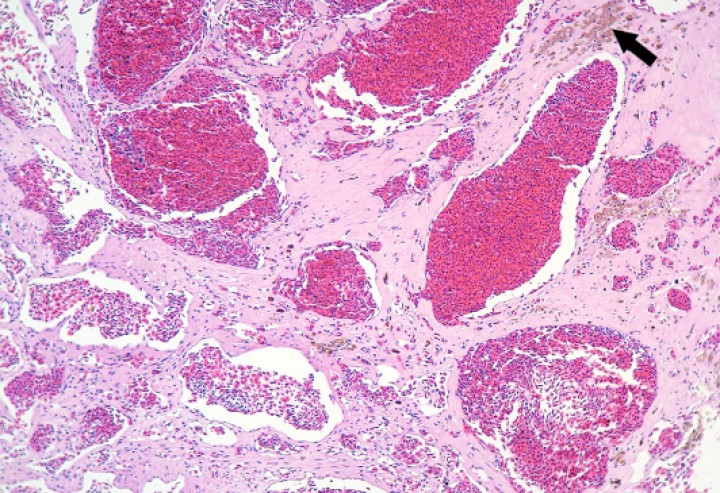

Figura 9

Pulmón; sapo buey (Rhinella schneideri). Se aprecia una proliferación neoplásica de cavernas vasculares revestidas por endotelio bien diferenciado (hemangioma) con focos de hemosiderosis (flecha) en el estroma de soporte de la neoplasia. Hematoxilina-eosina, x110.